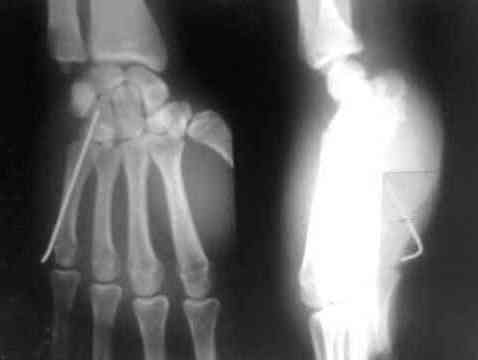

Дорогие коллеги,предлагаю посмотреть интересный случай. больной лечился в гипсовой лонгете 15 дней как ушиб.

правильный диагноз не был установлен.

я случайно взял эти снимки и посмотрел

поставил диагноз вывих 5 пястной кости.

больного я направил в область. его прооперировали. вынесены снимки.посмотрите.